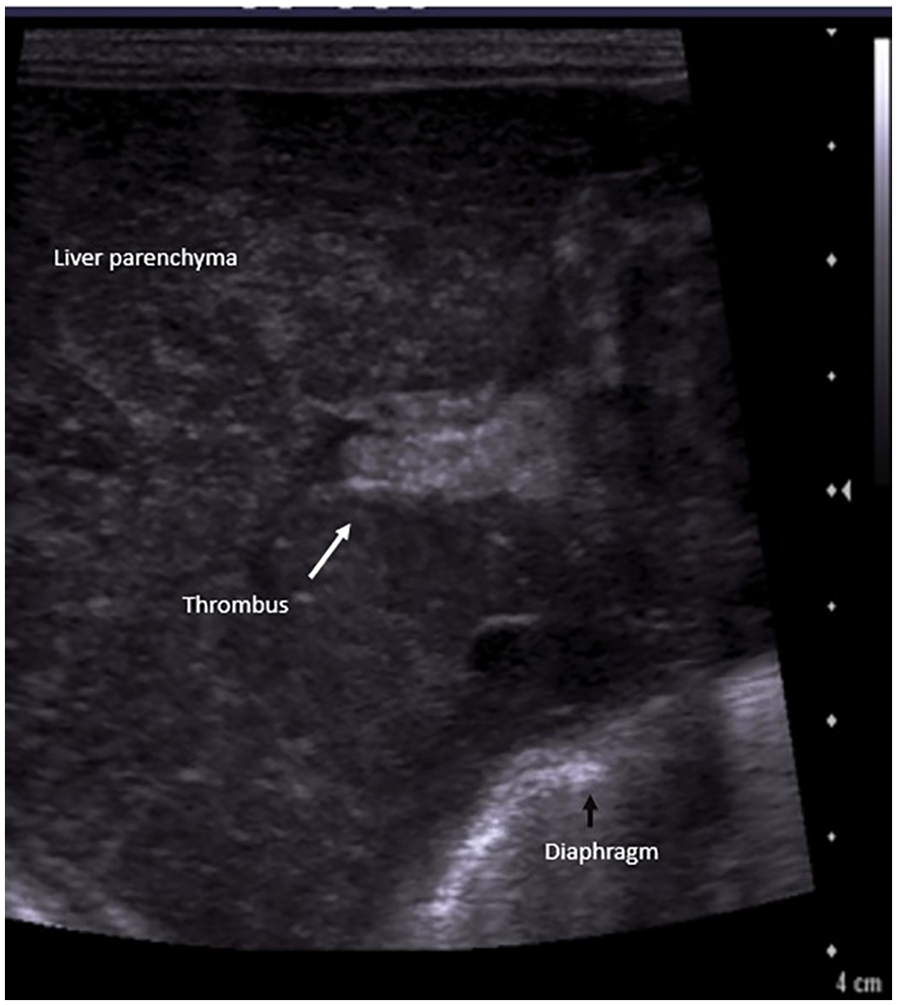

A preterm (GA 27 + 3 weeks) infant, weighing 1,120 g, was born to a gravida 2 mother via emergency cesarean section in view of antepartum hemorrhage and required delivery room intubation for resuscitation. The baby was transferred to the NICU, where it developed significant respiratory distress requiring mechanical ventilation. A chest x-ray showed a ground glass appearance of the lungs with air bronchograms, and surfactant was administered at 2 h of life. Umbilical venous and arterial catheters were secured and antibiotics commenced. The initial hemogram was normal. A second dose of surfactant was administered for high oxygen requirement, following which ventilator settings were weaned. On DOL 4, the neonate had an episode of pulmonary hemorrhage. Investigations revealed thrombocytopenia and a deranged coagulation profile. Blood products were administered, and the patient was placed on HFOV. Repeat blood cultures and endotracheal secretions grew Stenotrophomonas maltophilia, which was sensitive to fluroquinolones and ceftazidime; antibiotics were modified accordingly. The patient improved clinically. However, as thrombocytopenia persisted despite clinical improvement, adequate antibiotic coverage, and platelet transfusions, additional causes for thrombocytopenia were considered. A screening bedside ultrasound of the abdomen to screen for thrombosis in major vessels revealed an echogenic thrombus in the right and left portal vein, with a reformation of the distal portal vein (Figure 6). The umbilical lines were removed, and the antibiotics were continued for a total of 14 days. The patient was subsequently extubated and discharged on DOL 66. A repeat ultrasound abdomen prior to discharge showed normal flow through the portal vein.

Figure 6

Liver POCUS shows an echogenic thrombus (arrow) in the portal vein.

In acute stages, PVT appears iso/hypoechoic on gray scale ultrasound. Subsequently over the following days, the thrombus appears echogenic, and in late stages, calcification might be seen. Colour Doppler reveals absent or partial blood flow in the portal vein, or the formation of collaterals around the thrombotic segment (40).